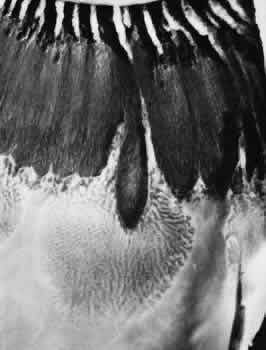

The anterior edge of the peripheral retina is theora serrata, an irregularly scalloped border; the irregularities are more pronounced nasally than temporally and have extreme individual variations in contour (Fig. 5). Dentate or toothlike processes extend anteriorly from the main contour of this bor-der, and bays or indentations extend posteriorly from the main contour of the ora serrata. At theora serrata, those projections of the retina toward the vitreous body are termed meridional folds. There is a concentration of dentate processes, ora bays, and meridional folds in the superior nasal quadrant and a progressive decrease in these morphologic features in the inferior nasal, superior temporal, and inferior temporal quadrants (Figs. 6 and 7). Although individual variations in ora serrata contour may be extreme, studies of adult human eyes demonstrate that both of a patient's eyes are remarkably similar and that statistically, the “average” ora serrata has 16 dentate processes, 1 large or giant dentate process, 10 ora bays, and 1 double ora bay.1,2

Fig. 5. Composite scale drawing depicts peripheral retina, ora serrata, ciliary body, and lens as viewed from posterior aspect. Ora serrata have more dentate processes and ora bays in the nasal quadrants than in the temporal quadrants.

Fig. 6. Peripheral fundus showing preequatorial retina, ora serrata, and inner surface of ciliary body (smooth portion, pars plana; portion with ciliary processes, pars plicata). Ora serrata in this nasal sector shows largely short dentate processes that are typical; that is, they align with valleys between ciliary processes. On right, a giant dentate process is atypical; that is, it aligns with a ciliary process. Aligned with and posterior to the atypical dentate process is a focus of retinal thinning (peripheral retinal excavation). (× 14.)